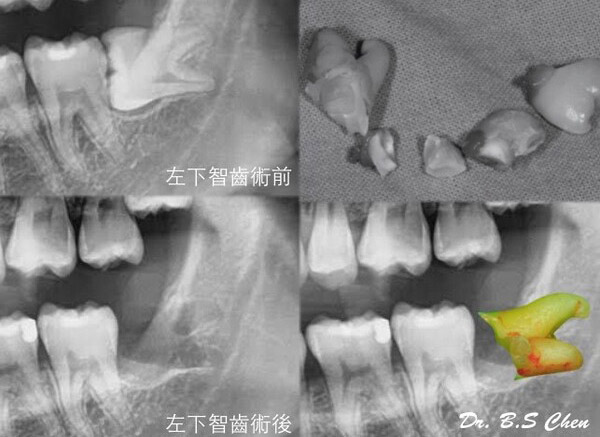

微創智齒手術案例分享